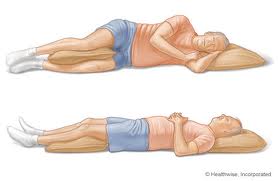

در این روش پزشک معالج ساق بیمار را در اطاق عمل و تحت بیهوشی عمومی جااندازی کرده و سپس اندام تحتانی را در گچ بلندی قرار میدهد. در چند روز اول پس از گچ گیری بیمار باید در منزل دراز کشیده و ساق را در سطحی بالاتر از سطح قلب خود نگه دارد تا از ورم آن جلوگیری کند. به بیمار توصیه میشود انگشتان پا را مرتبا حرکت دهد و عضلات چهارسر ران را بطور مرتب و بصورت ایزومتریک منقبض کند.